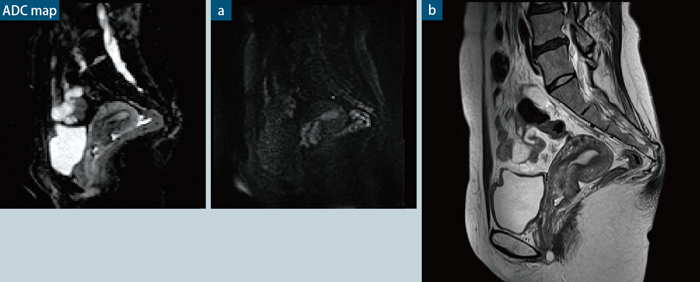

●症例4 子宮頸がん

拡散強調画像はダイレクトサジタルにて撮像。拡散強調画像,T2強調画像ともにスライス厚2.5mm

a:diffusion,sagital,TR/TE: 4800/75,スライス厚2.5mm, マトリックス:96×128,b-value: 1000,iPAT facotr:2,撮像時間:4分10秒(b-value:0,100,500,1000)

b:TSE,TR/TE:3500/81,スライス厚2.5mm,マトリックス:291×448,iPAT facotr:3,撮像時間: 1分34秒